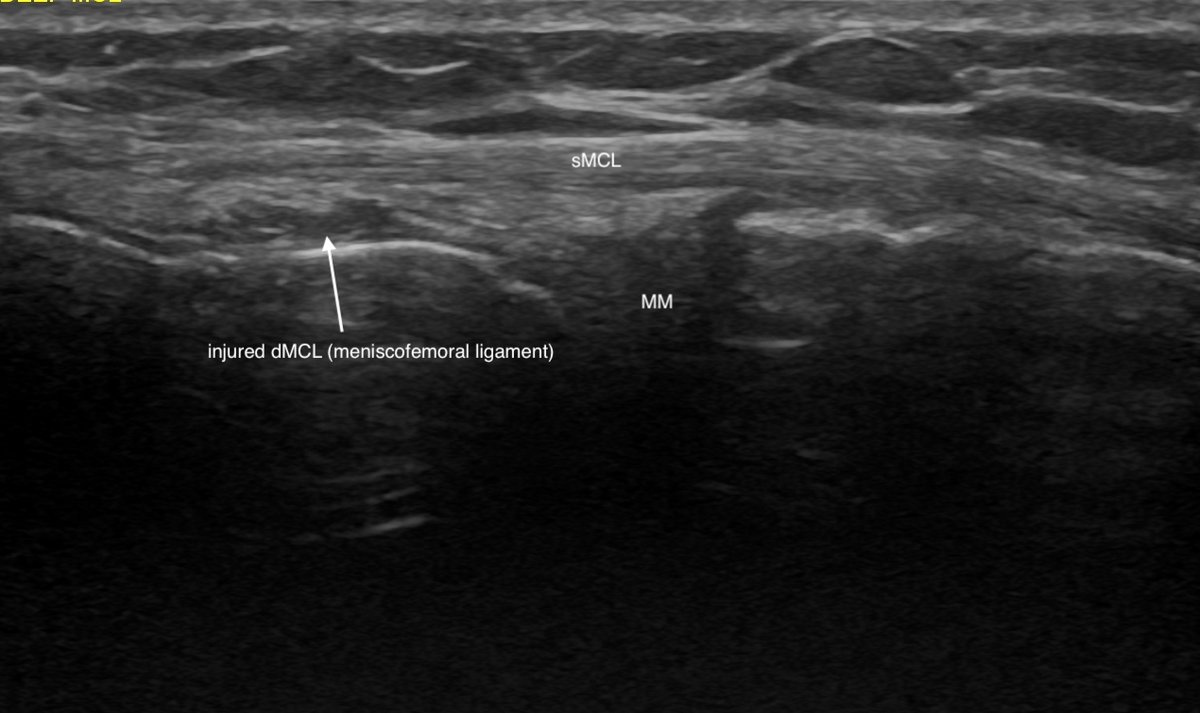

Caught edge of ski moving slowly on ice 1 year ago - abrupt valgus / external rotation

Immediate medial knee pain, but settled quite quickly

No effusion

Since, nagging medial aching particularly on rotational movement eg side pass football, pivoting in tennis (can be sudden / sharp) - lost confidence in knee

Pure lateral movements - side step - ok

Exam - some subtle increased travel on anteromedial glide. No overt valgus laxity vs contralateral side

Tender on firm palpation proximal MCL

POCUS - chronic 'sprain' (arrow) of deep MCL (meniscofemoral ligament) - superficial MCL intact, meniscus normal

These deep MCL injuries can niggle on for ages, the key symptom is rotational provocation